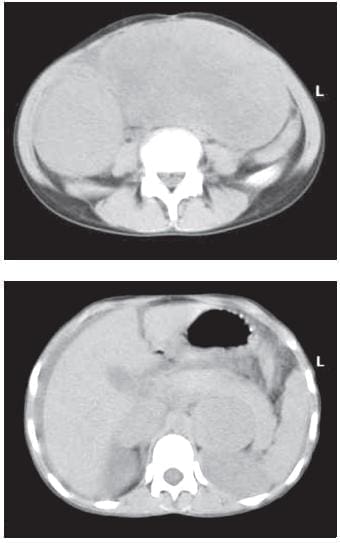

En la tomografía computadorizada (TC) de abdomen,se apreció una tumoración de grandes dimensiones en hipocondrio y flanco izquierdos, sin compromiso renal ni esplénico, y un nódulo redondeado y calcificado en la fosa ilíaca derecha (figuras 1 y 2).

FIGURAS 1 Y 2. TC de abdomen donde se observa el tumor de colon izquierdo y la adenopatía calcificada de la bifurcación de los vasos ilíacos derechos.